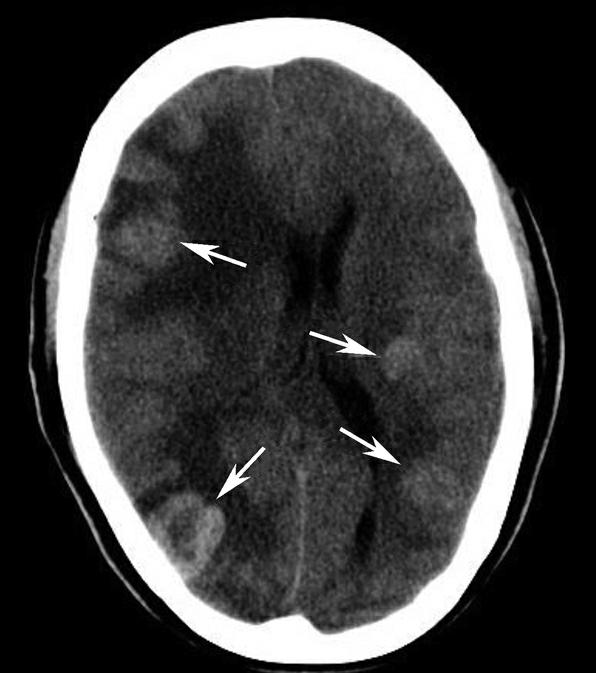

基底节为脑卒中的好发部位,与纹状动脉的解剖特点有关,深穿支动脉的破裂和栓塞可分别引起基底节区的出血和梗死(图1-2-32、图1-2-33)。

图1-2-32 脑出血

A.右侧壳核脑出血,形成高密度血肿(★);B.右侧丘脑出血,呈球形高密度影(箭)

图1-2-33 基底节区脑梗死

A.右侧丘脑梗死,病灶呈圆形低密度影(箭);B.左侧内囊膝部及后肢梗死,呈带状低密度影(箭)